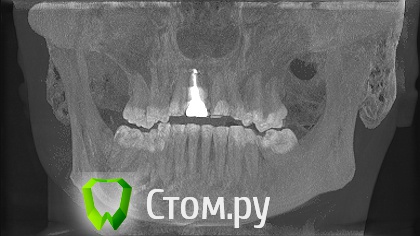

sergey765 Опубликовано 11 июня, 2014 Автор Поделиться Опубликовано 11 июня, 2014 посмотрите пожалуйста КТ. Ссылка на комментарий

Bier Опубликовано 11 июня, 2014 Поделиться Опубликовано 11 июня, 2014 это все не информативные кадры, в прикрепленных темах есть инструкция, выкладывайте КТ целиком, наш рентгенолог скачает и выложит срезы. 3 Ссылка на комментарий

sergey765 Опубликовано 12 июня, 2014 Автор Поделиться Опубликовано 12 июня, 2014 хорошо сейчас скидываю весь диск в рар архиве в файлообменник. люди добрые пожалуйста скачайте посмотрите. умоляю на коленях. ситуация у меня крайне серьезная. мне нужно чтобы хороший хирург посмотрел. в долгу не останусь. и если что у меня сильно там серьезное приеду к вам в клинику в москву/питер. а там что-то полюбас будет..... вчера когда делал КТ в частной клинике девочка (лет 20) смотрела, нифига вроде не поняла, сказала только у меня там инфекции полно (где там я не понял) и лунка удаленного зуба не заживает типа надо хирургу показать он вскроет прочистит т.е возможно когда мне зуб удаляли не прочистили там ничего... сейчас меня беспокоят боли в районе подбородка. самочувствие моё плохое. с кровати почти не встаю. все написано в начале данной темы.умоляю скачайте посмотрите. томограмма сделана программой iCATVision Ссылка на комментарий

sergey765 Опубликовано 12 июня, 2014 Автор Поделиться Опубликовано 12 июня, 2014 (изменено) ещё хочу добавить. когда у меня удаляли 5 недель назад мой зуб. из лунки выскочил какой-то кусок черного мяса размером почти с горошину. это не кровяной сгусток а именно кусок застывшиго черного мяса. крови почти не было. так во этот кусок мяса залез обратно в десну-челюсть только дня через 4. и видна в лунке была только челюсть желтого цвета и посередине дырка из кости куда этот кусок мяса залез. потом я пришел к врачу который удалял она мне на кость положила лекарство желтого цвета которое тупо застыло и не растворялось. стало как камень. от запаха этого лекарства я реально чуть не сдох. так было ещё дней 5. потом лунка затянулась но кусок желтой кости торчит досихпор. еще при удалении пол левой челюсти побелело. образовался какой-то белый налет на левой половине верхней и нижней десне. через 2-3 дня после удаления я провел пальцем по деснам и этот налет с десны снялся но остался белый комок на пальце которым я проводил по десне... еще у меня постоянно уже года 2 наверно из левого глаза идет временами гной... посмотрите на снимке там даже с левой стороны челюсти (правой снимка) есть какое-то черное пятно. Изменено 12 июня, 2014 пользователем sergey765 Ссылка на комментарий

sergey765 Опубликовано 12 июня, 2014 Автор Поделиться Опубликовано 12 июня, 2014 (изменено) и ещё. удаление было левая сторона нижней челюсти 3-й зуб... 2-й весь страшный вот в нём дофига инфекции. из-под десны там камень или гной идет фиг его знает. а в самом зубе какая-то белая фигня. ну его сказали можно типа вылечить. сейчас короче загружаю файл КТ. размер 310мб Изменено 12 июня, 2014 пользователем sergey765 Ссылка на комментарий